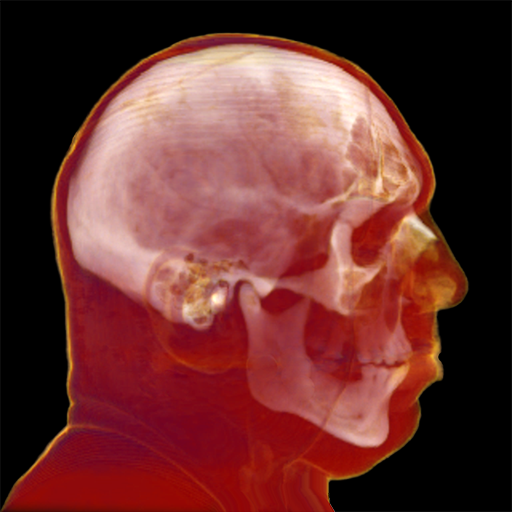

Rendering CT Scans

I mapped the scan's CT density to body tissues (bones, cartilage, muscle, fat, skin) assigning color/transparency to each tissue type.

When WebGL first came out, I did a weekend project to test tissue color/alpha mapping - and evaluate WebGL performance. I rendered CT scan slices as texturemap planes (billboards), resulting in the expected gap band artifacts you can see along the side view.To support translucency, the slices must be rendered in back-to-front order. I avoided sorting slices by using model-view orientation to determine which slice is to the right of the eye view, then using a reversed slice list on the other side.

My follow-up project was a ray casting iPhone app to display CT and MRI scans.

Optimized Ray Casting

My innovations for this project were to create a new ray casting algorithm that works both back-to-front and front-to-back for optimized translucency, develop tissue segmentation classifiers, and to generate a normal map from tissue segments.I also created a fast algorithm for determining how many rows and columns are in texturemaps, to support user-supplied images with no metadata.

The app renders 2D grayscale CT/MRI scans into 3D color in real-time. Through real-time segmentation, I'm able to filter/display selected body materials. Here's a video of the app: